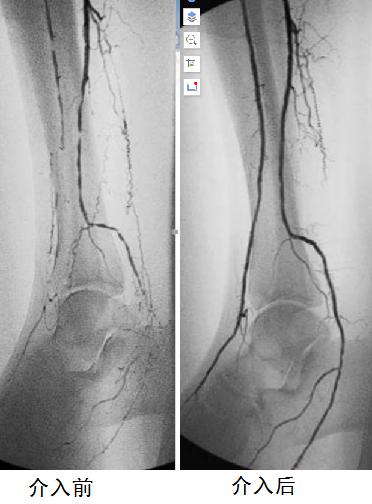

其四,血管成形术。主要是指用球囊导管插到已经初步开通但仍然明显狭窄的病变血管部位,然后充盈球囊,使狭窄处被动地扩张,从而恢复血管的腔径。

球囊导管扩张成形术

血管造影可清晰显示狭窄闭塞情况,腔内介入快捷有效